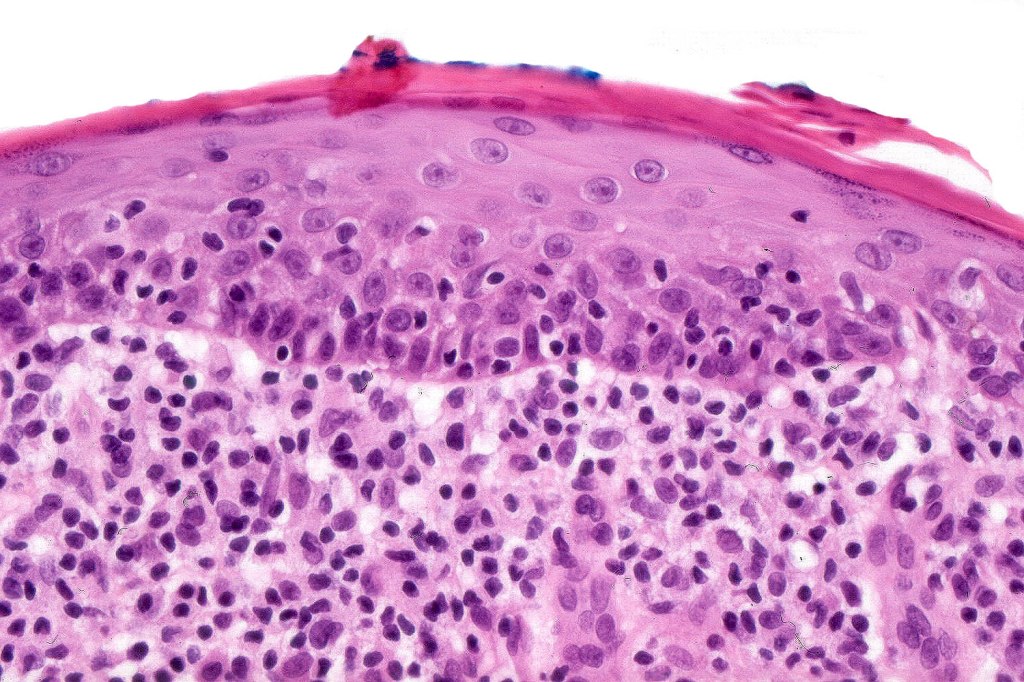

•Variable MF-like epidermal features

•Established lesions are readily recognizable & characterized by a dense infiltrate throughout the dermis &extending into subcutaneous fat

•Atypical, hyperchromatic lymphocytes, Sezary cells, histiocytes, plasma cells, eosinophils & characteristic multinucleate giant cells (innumerable nuclei resembling a shoal of fish)

•Lymphophagocytosis is generally marked

•Discrete granulomata often evident & in some cases may be the dominant feature obscuring the background lymphomatous infiltrate